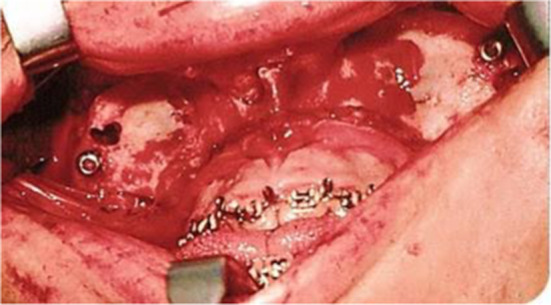

After the orbital and zygomatic osteotomy is finished, the intraoral osteotomies are performed. The approach is through an extended vestibular incision, from the second molar of one side to the opposite second molar. The osteotomy is performed from the pterygoid processes to the orbital floor, 5 mm anterior to the inferior orbital fissure. For this, the surgical guide is needed to perform symmetric osteotomies with the oscillating saw. Note that the green surgical guide is used in this area and it also possess a metal hook located in its most superior portion to protect the inferior orbital contents (Figs. 7, 8) [2, 9]. The objective is to make the craniofacial disjunction symmetrical and in accordance with the surgical planification. The millimetres advanced in the zygomatic bone correspond to the same amount of advancement in the pterygoid region.

Fig. 7.

The surgical guide is positioned over the pterygomaxillary buttress in an anterior view